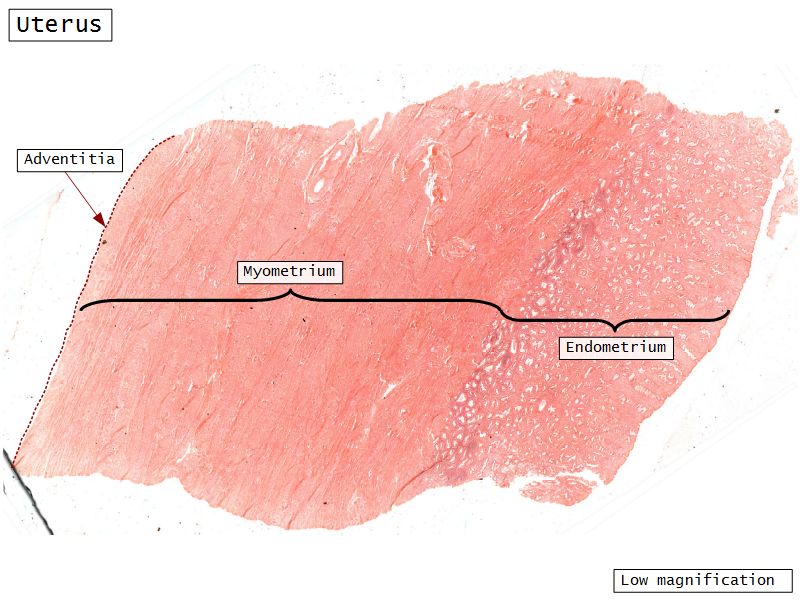

Uterus

Uterus

Three layers

- Endometrium

- Formation placenta

- Myometrium

- Enlarge during pregnancy

- Expulsion fetus & placenta

- Adventitia

Myometrium

- Enlarge during pregnancy

- Expulsion fetus & placenta

- 3 layers indistinct smooth

- Inner longitudinal/oblique

- Central circular

- Large blood vessels

- Stratum vasculare

- Outer longitudinal/oblique

Adventitia

- Or serosa

- Covers myometrium